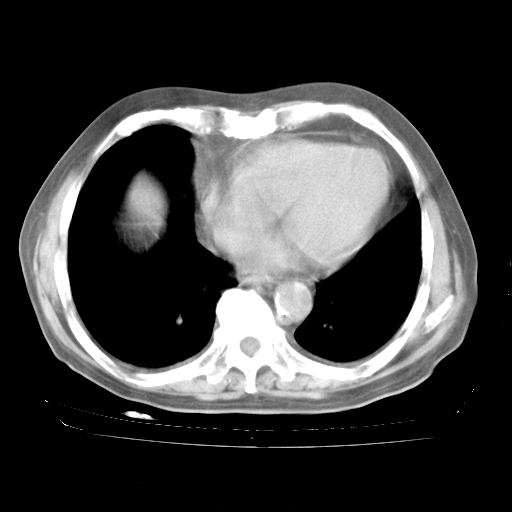

4月28日肺部CT

1、108#的是4月14日的胸部CT(发此贴时还没看着28日的CT)。14日的胸部CT其实已经出现改变(如108#所述),个人认为28日的胸部CT除纵膈窗疑似有双侧胸膜增厚或少量胸积液(可行胸部B超明确)外,与4月14日对照病变有所加重;2、已经给予“异烟肼、利福平、乙胺丁醇”抗痨治疗?如果是,甲强龙80mg可缓慢减量;如果环磷酰胺已停用,暂不使用;3、中性粒细胞92%,明显升高,目前体温情况?注意合并细菌感染可能,使用左氧氟沙星情况下,是否联用B-内酰胺类抗菌药物?另外是查免疫全套非风湿全套。